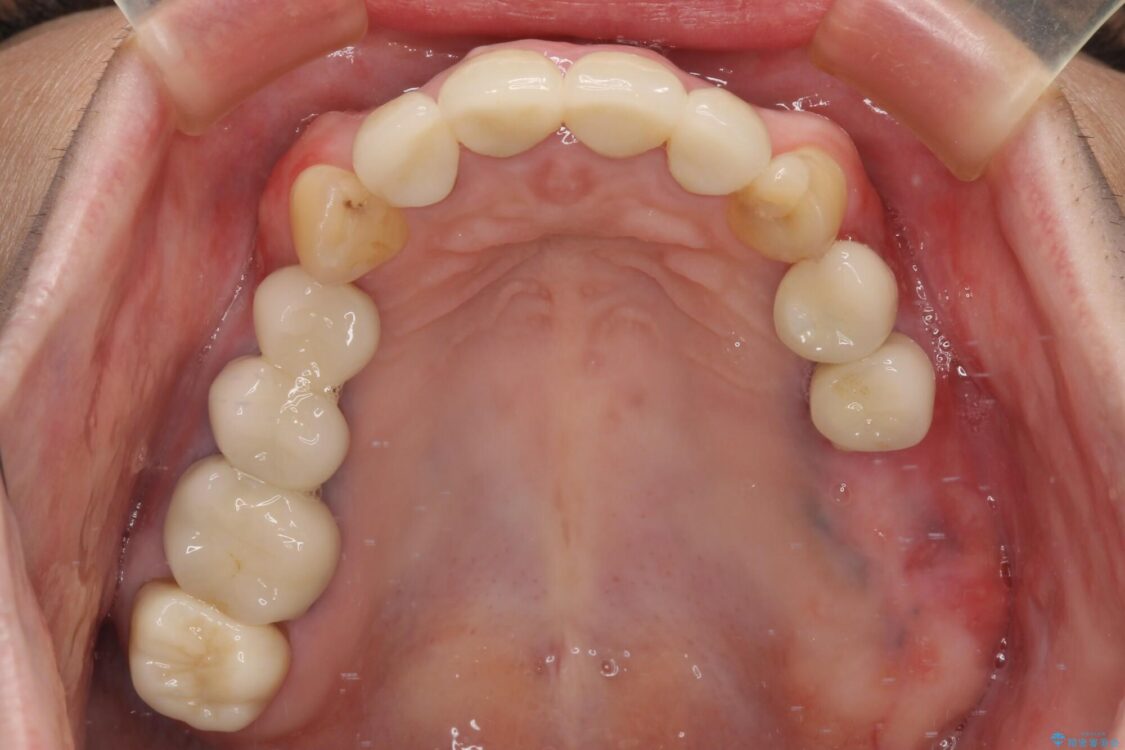

治療後

• 仮歯のまま放置した前歯 オールセラミッククラウンで自然な前歯に 治療後画像